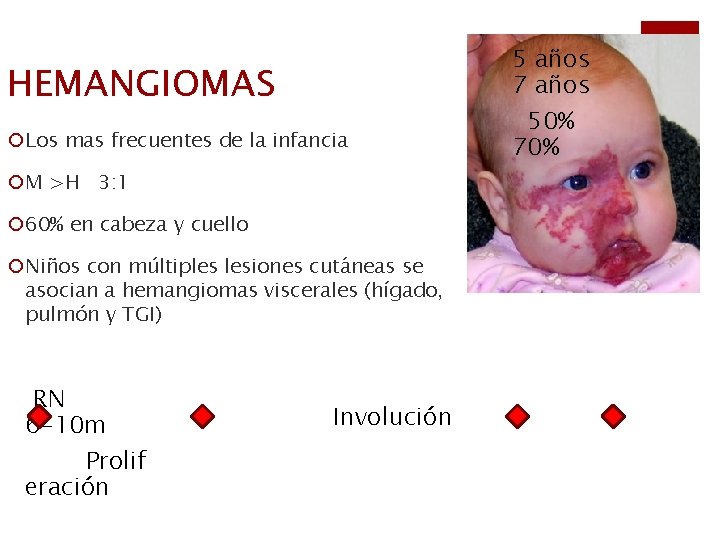

HEMANGIOMAS ¡Los mas frecuentes de la infancia ¡M >H 3: 1 ¡ 60% en cabeza y cuello ¡Niños con múltiples lesiones cutáneas se asocian a hemangiomas viscerales (hígado, pulmón y TGI) RN 6 -10 m Prolif eración Involución 5 años 7 años 50% 70%